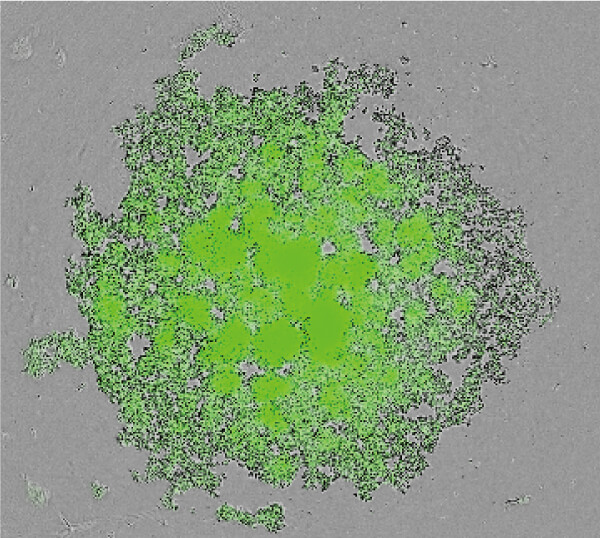

NoviSightを用いた病理マーカー解析

- 肺腺がん由来F-PDO®(RLUN14、RLUN20)と肺扁平上皮がん由来F-PDO®(RLUN16、RLUN21)を、肺腺がんマーカーのTIF1、肺扁平上皮がんマーカーのp63に対する抗体を用いて、免疫染色を行った。

- 病理診断と同様に、肺腺がん由来F-PDO®はTIF1抗体で、肺扁平上皮がん由来F-PDO®はp63抗体で染色された。

- それぞれのF-PDO®の細胞塊あたりの陽性細胞率をNoviSightを用いて算出した。その結果、有意差をもって、それぞれのマーカーに対して高い陽性率を示した。

| TTF1(肺腺がんマーカー) | |||

| p63(肺扁平上皮がんマーカー) | |||

|---|---|---|---|

| 腺がん RLUN14 | 扁平上皮がん RLUN16 | コロイド腺がん RLUN20 | 扁平上皮がん RLUN21 |

これらのデータはオリンパス株式会社との共同研究により取得しました